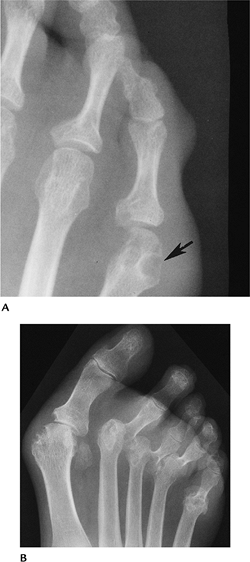

![]() |

FIGURE 6-73 (A)

AP view of the great toe with asymmetric joint destruction and bone proliferation at the base of the distal phalanx characteristic of seronegative spondyloarthropathies. (B) Characteristic swelling and joint space changes in the great toe with ankylosis of the fourth toe caused by psoriatic arthritis. |